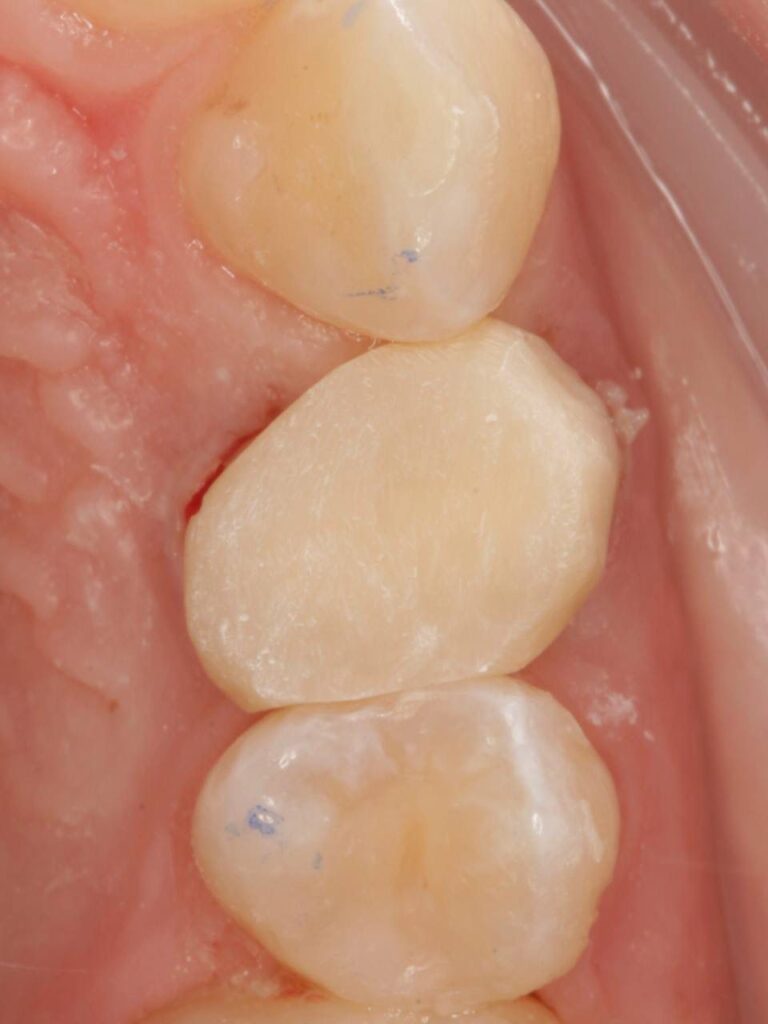

Специализация: терапия(эндодонтия), ортопедия, имплантология.